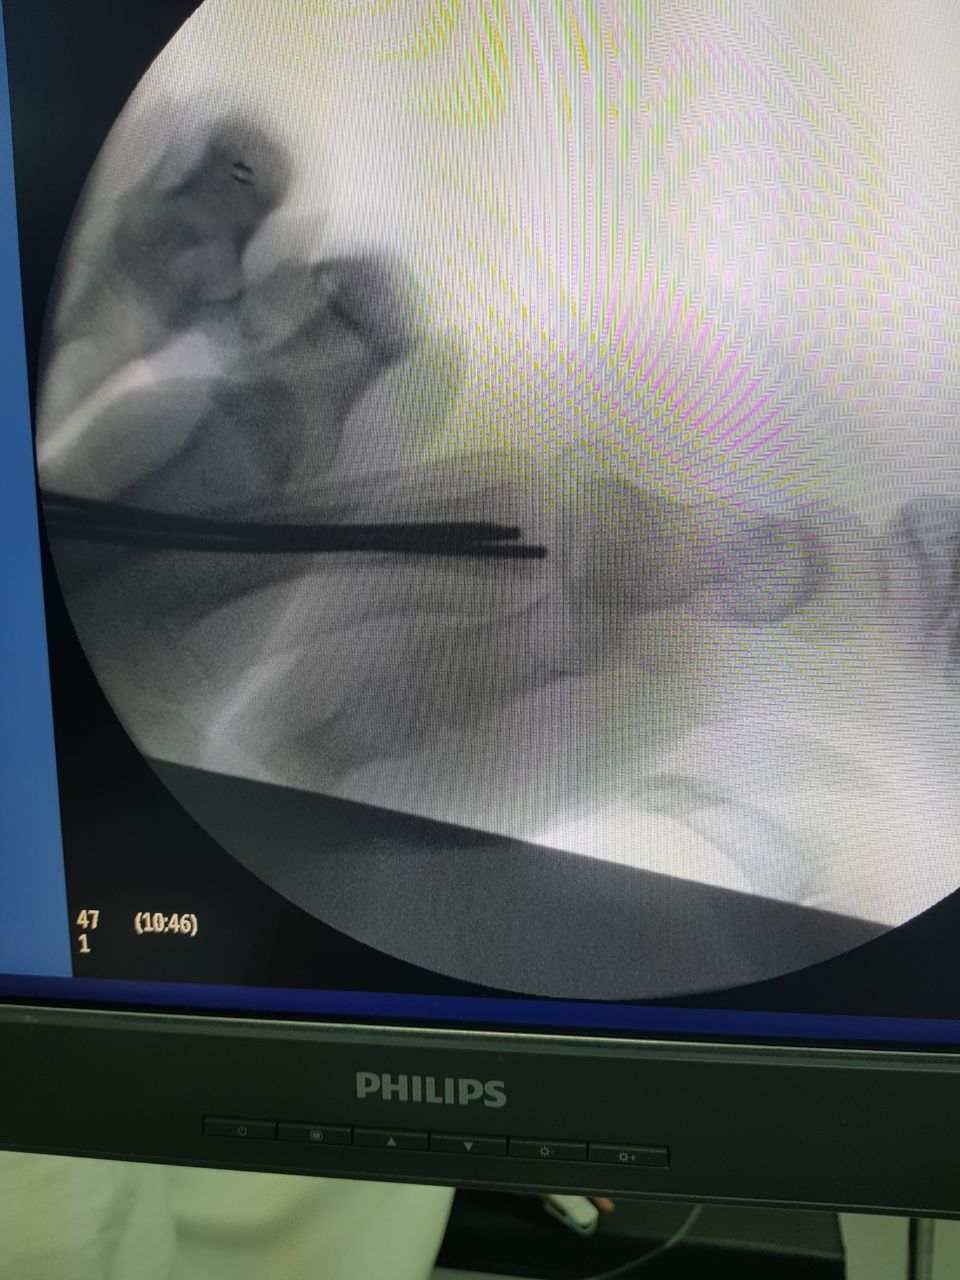

نجح فريق طبي متخصص في مستشفى أبوعريش العام بقيادة طبيب العظام الدكتور محمد الشافعي، والأطباء المساعدين الدكتور أيمن مطاوع، والدكتور ضيفي محمد، وطبيب التخدير الدكتور عباس، في إجراء جراحة عاجلة ونادرة لحالة طفل تعرض لحادث مروري نتج عنه خلع مشطيات اليد اليمنى بشكل كامل.

وتمثلت الجراحة في الرد المغلق وادخال الاسلاك المعدنية (IC.wires) من نهاية المشطيات عن طريق فتحات لا تتجاوز ٢مم وتثبيتها بالرسغ.

وتكمن صعوبة الجراحة في صغر سن الطفل وصغر عظام الطفل والتورم الشديد.